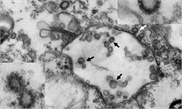

Mongolia authorities confirms teenage boy died of plague

A suspected case of plague in western Mongolia has been confirmed by lab test results, the country's health ministry reported on Tuesday.